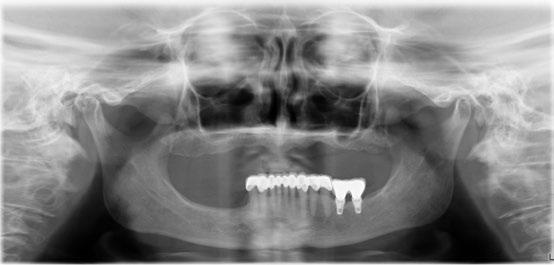

En nuestro caso, al igual que en la aviación, quien nos dio la “suelta” fue el Dr. Bertil Friberg. Así pues, en la década de 1980 tratamos nuestros primeros tres casos con implantes osteointegrados. Dos puentes fijos mandibulares (uno sobre 4 implantes y otro sobre 5) y una sobredentadura con una barra soportada por tres.

El primero de nuestros pacientes, de 32 años, había perdido su incisivo central superior derecho a los 12 años y el segundo, de 29 años, había perdido su incisivo lateral superior izquierdo en un accidente de tráfico ocurrido siete años antes. (Figura 4)

• Mantener un periodo de al menos seis meses en el maxilar superior antes de someter los implantes a carga funcional. En ambos casos se utilizaron fijaciones de titanio mecanizado de 15 mm de longitud y 3,75 mm de diámetro (Nobelpharma). (Figura 5)

Durante los 17 años siguientes, ambos implantes funcionaron de manera satisfactoria, cumpliendo correctamente su cometido tanto en el plano funcional como en el estético. Sin embargo, en 2005 fue necesario sustituir la corona del incisivo central debido a una nueva fractura. Para ello se recurrió a la tecnología disponible en ese momento: se diseñó un pilar en resina acrílica, que posteriormente fue escaneado y fresado en zirconio (Procera), sobre el cual se confeccionó una corona totalmente cerámica en alúmina. (Fig. 9 y 10)

Dos años después de la colocación de esta nueva restauración, observamos que el nivel óseo, que se había mantenido estable durante 17 años, mostraba una mejora notable tras la colocación del nuevo pilar y la nueva corona. Este cambio se aprecia claramente al comparar las radiografías de 2005 con 2007, situación que se ha mantenido hasta la actualidad. (Fig. 11) Es muy probable que el cambio óseo observado se deba a que, para la nueva restauración, se utilizó un pilar mecanizado mediante

maquinaria de precisión en zirconio (Procera), lo que permitió reducir significativamente el espacio en la interfase pilar-implante (gap). Asimismo, no es descartable que a este cambio también haya contribuido la disminución de los micromovimientos del pilar sobre la cabeza del implante, al haberse utilizado un tornillo TorqTiite (Nobel Biocare) ajustado con llave dinamométrica a 35 Ncm, en lugar de hacerlo manualmente a 10–15 Ncm, como se había realizado con el pilar original de Jemt.

También la corona del lateral se volvió a rehacer en el año 2025 al mismo tiempo que se restauraron 23 y 24, utilizando la tecnología disponible hoy en día mediante impresión digital. (Fig. 12 a 16)

Para concluir creo que podemos afirmar que, a pesar de haber sido tratados ambos pacientes en 1987 —cuando nuestra curva de aprendizaje era aún incipiente—, estos dos casos documentan de manera inequívoca que los principios fundacionales de la implantología desarrollados por P. I. Brånemark continúan plenamente vigentes. Naturalmente, en las últimas décadas hemos sido testigos de múltiples variaciones y avances que han contribuido a perfeccionar los procedimientos y optimizar los resultados; sin embargo, la esencia permanece inalterada.

La estabilidad clínica, la integración ósea y la predictibilidad pueden mantenerse durante décadas si se seleccionan cuidadosamente los casos, se respetan los protocolos y, por supuesto, se lleva a cabo un seguimiento clínico riguroso.